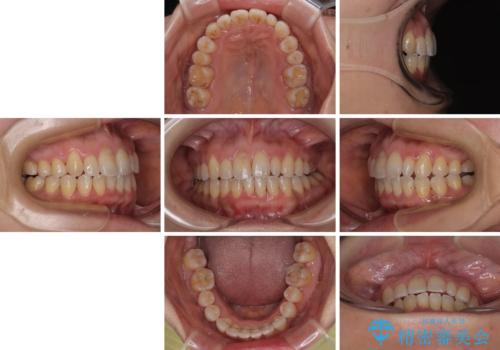

骨格的なズレを歯列矯正でカバー ワイヤー装置での非抜歯矯正

- 前歯のデコボコと咬み合わせの悪さを気にして来院された患者様です。

下顎骨が左側にズレて成長してしまったため、左側の咬み合わせが上下反対になっている状態でした。

そこまでの処置は望んでいらっしゃらなかったため、歯列矯正でのカムフラージュにより咬み合わせを改善することとしました。

予想通り左側の咬み合わせの調整に苦労をしましたが、最終的には違和感のない咬み合わせを達成することができました。